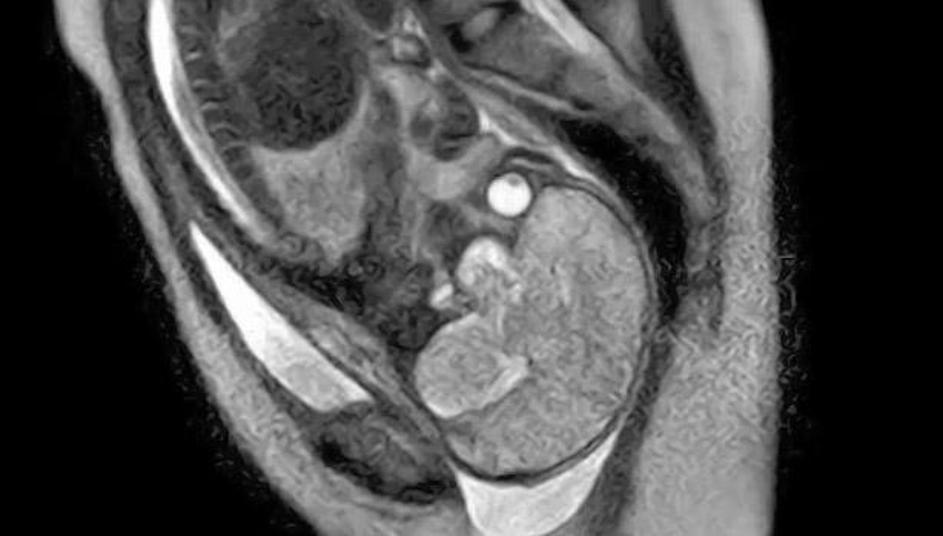

porod, snemanje, magnetna resonanca Poporodni pogled v notranjost maternice brez placente. Žurnal24 porod, snemanje, magnetna resonanca